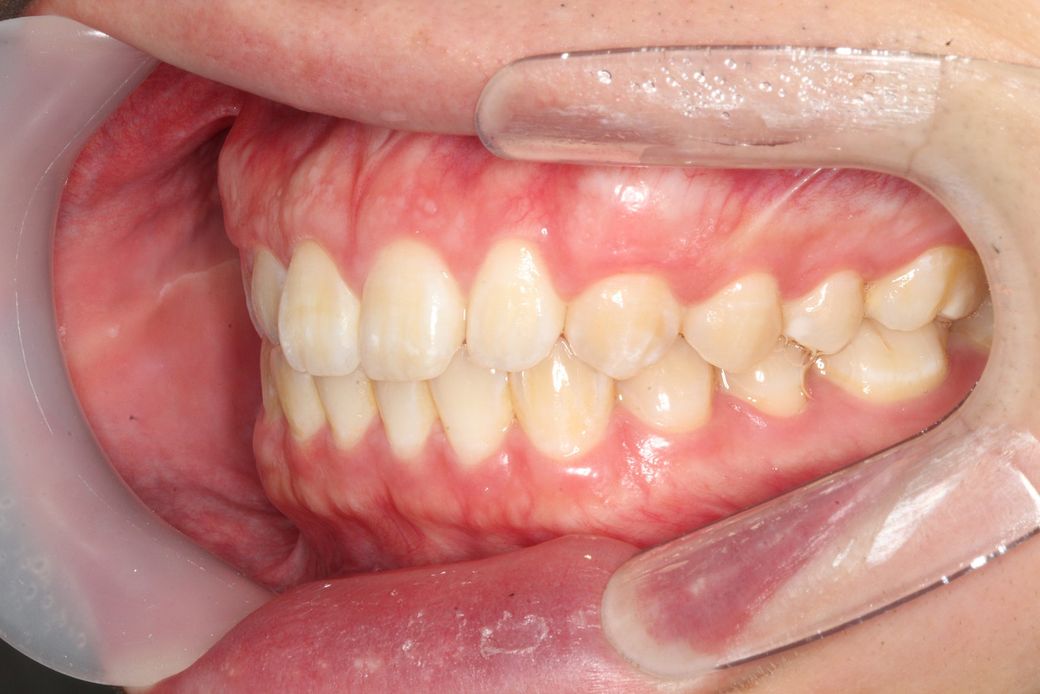

코 끝과 턱 끝을 연결한 선인 에스테틱 라인을 기준으로, 입술이 전방으로 돌출되어 보이는 상황으로 보입니다.

발치교정으로 앞니를 후방으로 당기거나 비발치 교정으로 전체 치열을 후방으로 당김으로써 돌출 정도를 완화할 수 있습니다.

대개 발치교정에 비해 비발치 교정시 돌출 개선 정도는 낮을 수 있습니다.

말씀하신 돌출입인지 아닌지는 연조직 사진 등도 모두 필요합니다. 지금은 골격적인 자료들만 있기 때문에 상악이나 하악의 발달 정도가 정상 범위에서 벗어나더라도 밖으로 보이는 연조직에서 차이가 있다면 돌출입이 될 수도 있고 안될 수도 있습니다. 따라서 지금의 자료로는 정확한 판단이 어렵습니다.

지금 자료로 보았을 때 심미적으로 비발치나 발치 교정을 하더라도 큰 변화는 기대하기 힘들 것으로 보입니다.

많이 부정교합이 심한 편은 아니지만 환자가 볼때 입술이 튀어 나온 것 같아 신경이 쓰인다면 교정으로도 어느정도는 조절이 가능합니다.